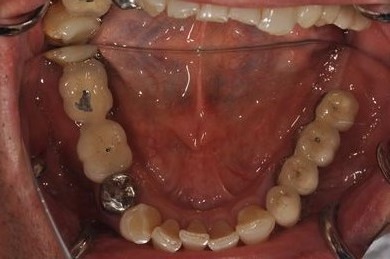

| 性別/年齢 | 男性 / 58歳 | ||||||||||||||||||||||||||||||||

| 主訴 | ブリッジがだめになったため、現在は部分入れ歯を使用しているが、インプラント治療を検討している。 | ||||||||||||||||||||||||||||||||

| 治療方針 | 左上奥の欠損部分をインプラント治療にて、機能的・審美的回復を行う。 | ||||||||||||||||||||||||||||||||

| 治療内容 | インプラント3本(GBR)、ハイブリッドセラミッククラウン3本 | ||||||||||||||||||||||||||||||||

| 総治療費 | 791,520円 | ||||||||||||||||||||||||||||||||

| 治療期間 | 10ヶ月 |